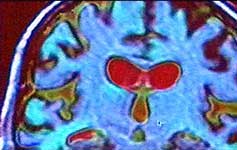

In this week's Leading Edge Geoff Watts talks to moral philospher-turned-neuropsychologist Joshua Greene at Princeton University about his research using functional Magnetic Resonance Imaging (MRI) to watch the brain activity of people making different kinds of moral judgements. In one experiment, Greene and his team gave a series of moral dilemmas for subjects placed in the MRI scanner to ponder. There were two categories of moral problem that they were particularly interested in comparing which the team have labelled impersonal and personal respectively.

For the majority of people, the 'personal'-style of dilemma is a greater challenge and they tend to take much longer to make a decision. In the MRI scans, the impersonal tends to result in an increased activity in abstract reasoning parts of the brain whereas the second 'personal' dilemma results in a more complicated pattern. In people who ponder this for sometime before making a decision, brain areas linked to social and emotional behaviour increase in activity as well as the abstract reasoning areas, together with an area (the anterior singulate cortex) which is active when different urges are in conflict.

Joshua Greene interprets the observations in terms of two mental domains of different evolutionary age in conflict - the ancestral primate social-emotional mind (which he says recoils from pushing the man off the bridge) and the more recently evolved abstract-reasoning capacity which is doing the Utilitarian numbers game. He believes an understanding of how our brains deal with moral judgements may help to us to make 'better' moral decisions.